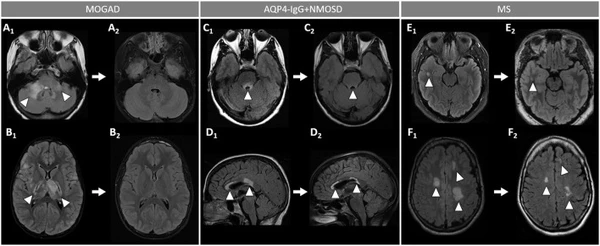

Магнитно-резонансная томография: картина отличается вариабельностью и не имеет патогномоничных признаков, часто напоминая другие воспалительные заболевания центральной нервной системы. Однако некоторые особенности позволяют заподозрить данный диагноз[4]:

- поражение головного мозга демонстрирует высокую вариабельность. У детей часто наблюдается картина острого диссеминированного энцефаломиелита, в то время как у взрослых очаги в мозге на момент диагностики выявляются менее чем в половине случаев. Характерно наличие немногочисленных, но крупных очагов, обычно двусторонних, с нечёткими контурами. У детей чаще вовлекаются ядра ствола мозга. Легкоменингеальное усиление встречается редко, как изолированно, так и в сочетании с корковыми поражениями. Вариабельное паренхиматозное усиление может затрагивать ствол мозга, серое и белое вещество, перивентрикулярные области;

- поражение зрительных нервов наблюдается у большинства пациентов, обычно в виде двустороннего неврита с вовлечением передних отделов. Характерны выраженный отёк нервов, приводящий к их извитости и отёку диска зрительного нерва. Типичным признаком является оптический периневрит — воспаление оболочки зрительного нерва. Также может отмечаться периорбитальное и интраорбитальное усиление. Вовлечение хиазмы и зрительных трактов встречается нечасто;

- поражение спинного мозга обычно носит центральный характер, затрагивая как серое, так и белое вещество. Наблюдаются как протяжённые, так и короткие очаги, которые могут сочетаться. Поражение серого вещества формирует характерный Н-признак на аксиальных срезах и тонкие линейные сигналы на сагиттальных изображениях. Часто преимущественно поражается нижний отдел спинного мозга. Важным дифференциальным признаком является лептоменингеальное усиление.